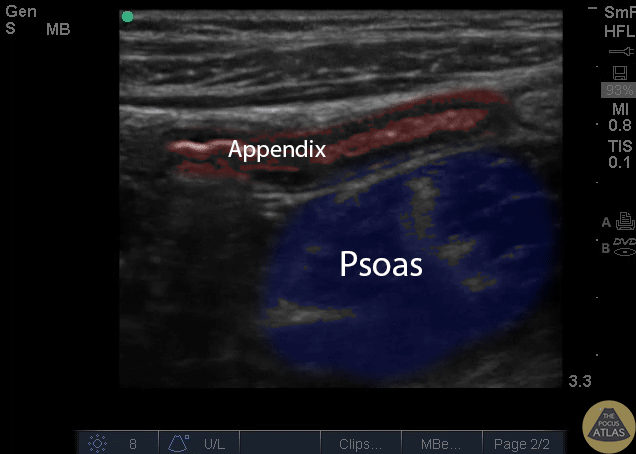

Colorized Appendicitis - Labeled and Colorized Appendix and Psoas

Images provided by Sathya Subramaniam - Children’s Hospital of Philadelphia, edited by Matthew Riscinti - Kings County Emergency Medicine